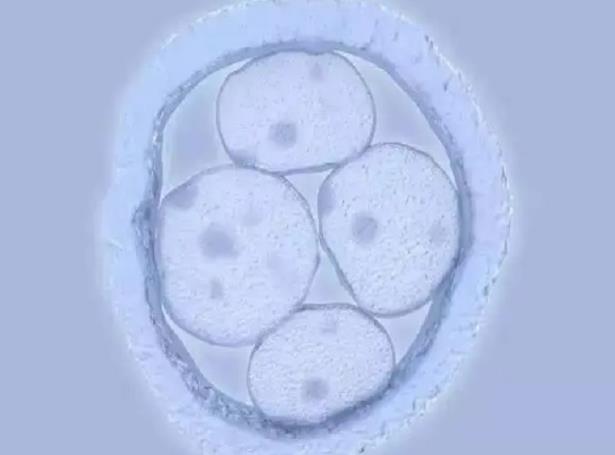

因为老公精子质量不是很好,就去医院做了二代试管,在周三的时候去医院移植了两枚二级胚胎,刚开始没有异常情况出现,就是感觉腰有点酸痛,不过昨天晚上上厕所的时候,发现内裤上有褐色分泌物印记,因为只有几滴,就没有在意,但是今天早上起来,发现内裤上有一小滩分泌物,在网上搜索了一下,说有可能是胚胎移植失败排出来了,但我觉得不是很像,所以想问一下胚胎排出后是什么样的呢?知晓自己是否排卵其实有很多的办法,其中大家用的最多的就是排卵试纸了,其实除了排卵试纸,还有计算排卵日期、基础温度测量和观察宫颈粘液等四种办法来判断,所以我们如果掌握这四种办法的话,就能够轻轻松松的知晓自己的排卵规律了,更重要的是就能够更好的准备备孕。内蒙古试管婴儿医院排名哪家好,2023内蒙古中医药研究所试管成功率预估